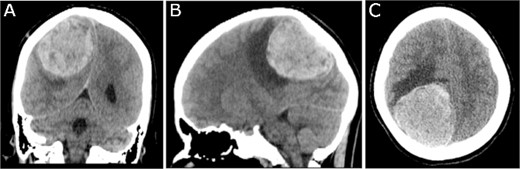

A 19-year-old woman presented with 2 months of intractable holocephalic headaches associated with nausea, occasional emesis, and generalized weakness which worsened over the 5 days preceding presentation. She had no past medical history and was not taking any regular prescribed medications. A computed tomography (CT) head (Fig. 1) revealed a right parietal mass measuring 6.2 × 5.5 × 5.8 cm. Her magnetic resonance imaging (MRI) re-demonstrated a large right parietal extra-axial mass as well as similar lesions in the right temporal lobe, with diffuse increased T1 signal without corresponding enhancement (Fig. 2).

Preoperative MRI; (A) pre-contrast, (B) post-contrast T1-weighted, and (C) T2-weighted axial MRI scans show a large right parietooccipital extra-axial mass with diffusely increased T1 signal without corresponding enhancement; (D, E) axial post-contrast T1-weighted MRI scans show two discrete lobular lesions along the medial aspect of the right temporal lobe and posterior cortical surface of the temporal lobe respectfully.